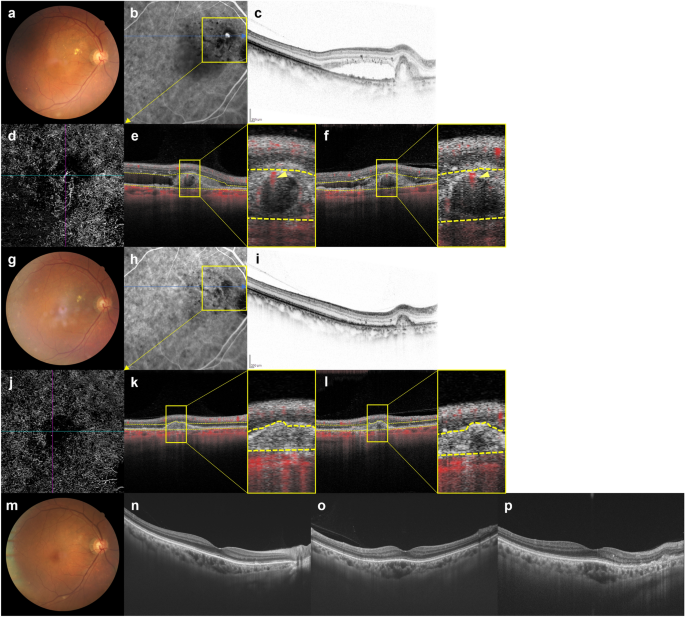

Images of the right eye of an 87-year-old man with polypoidal choroidal vasculopathy in the group with disappearance of blood flow signals within polypoidal lesions. (a–f): Baseline. Best corrected-visual acuity (BCVA) of the right eye is 0.16 logarithm of the minimal angle of resolution (logMAR) units. (a) Color fundus photograph shows a protruding lesion with serous retinal detachment (SRD) and hard exudates superotemporal to the optic disk. (b) Indocyanine green angiography (ICGA) shows a polypoidal lesion with a branching neovascular network (BVN). (c) Optical coherence tomography (OCT) B-scan image through the polypoidal lesion shows a sharp-peaked pigment epithelial detachment (PED) with SRD. (d) OCT angiography (OCTA) en face image shows blood flow signals corresponding to the polypoidal lesion and the BVN. (e, f) OCTA B-scan images (e: horizontal, f: vertical) show blood flow signal in the sub-RPE ring-like structure corresponding to the polypoidal lesion (arrowheads). (g–l) 3 months after the initial treatment. BCVA of the right eye is − 0.08 logMAR units. (g) Color fundus photograph shows no SRD. (h) ICGA shows complete regression of the polypoidal lesion. (i) OCT B-scan image shows the sharp-peaked PED to be diminished without SRD. (j) OCTA en face image shows no blood flow signal corresponding to the polypoidal lesion and the BVN. (k, l) OCTA B-scan images (k: horizontal, l: vertical) show no blood flow signal at the edge of the PED, which had been detected at baseline. (m–p) One year after the initial treatment. BCVA of the right eye is − 0.08 logMAR units. In total, 6 injections were given during the 1-year study period. (m) Color fundus photograph shows no exudative changes. (n–p) OCT B-scans through the fovea (n: horizontal, o: vertical, p: radial through the regressed polypoidal lesion) show dry macula.